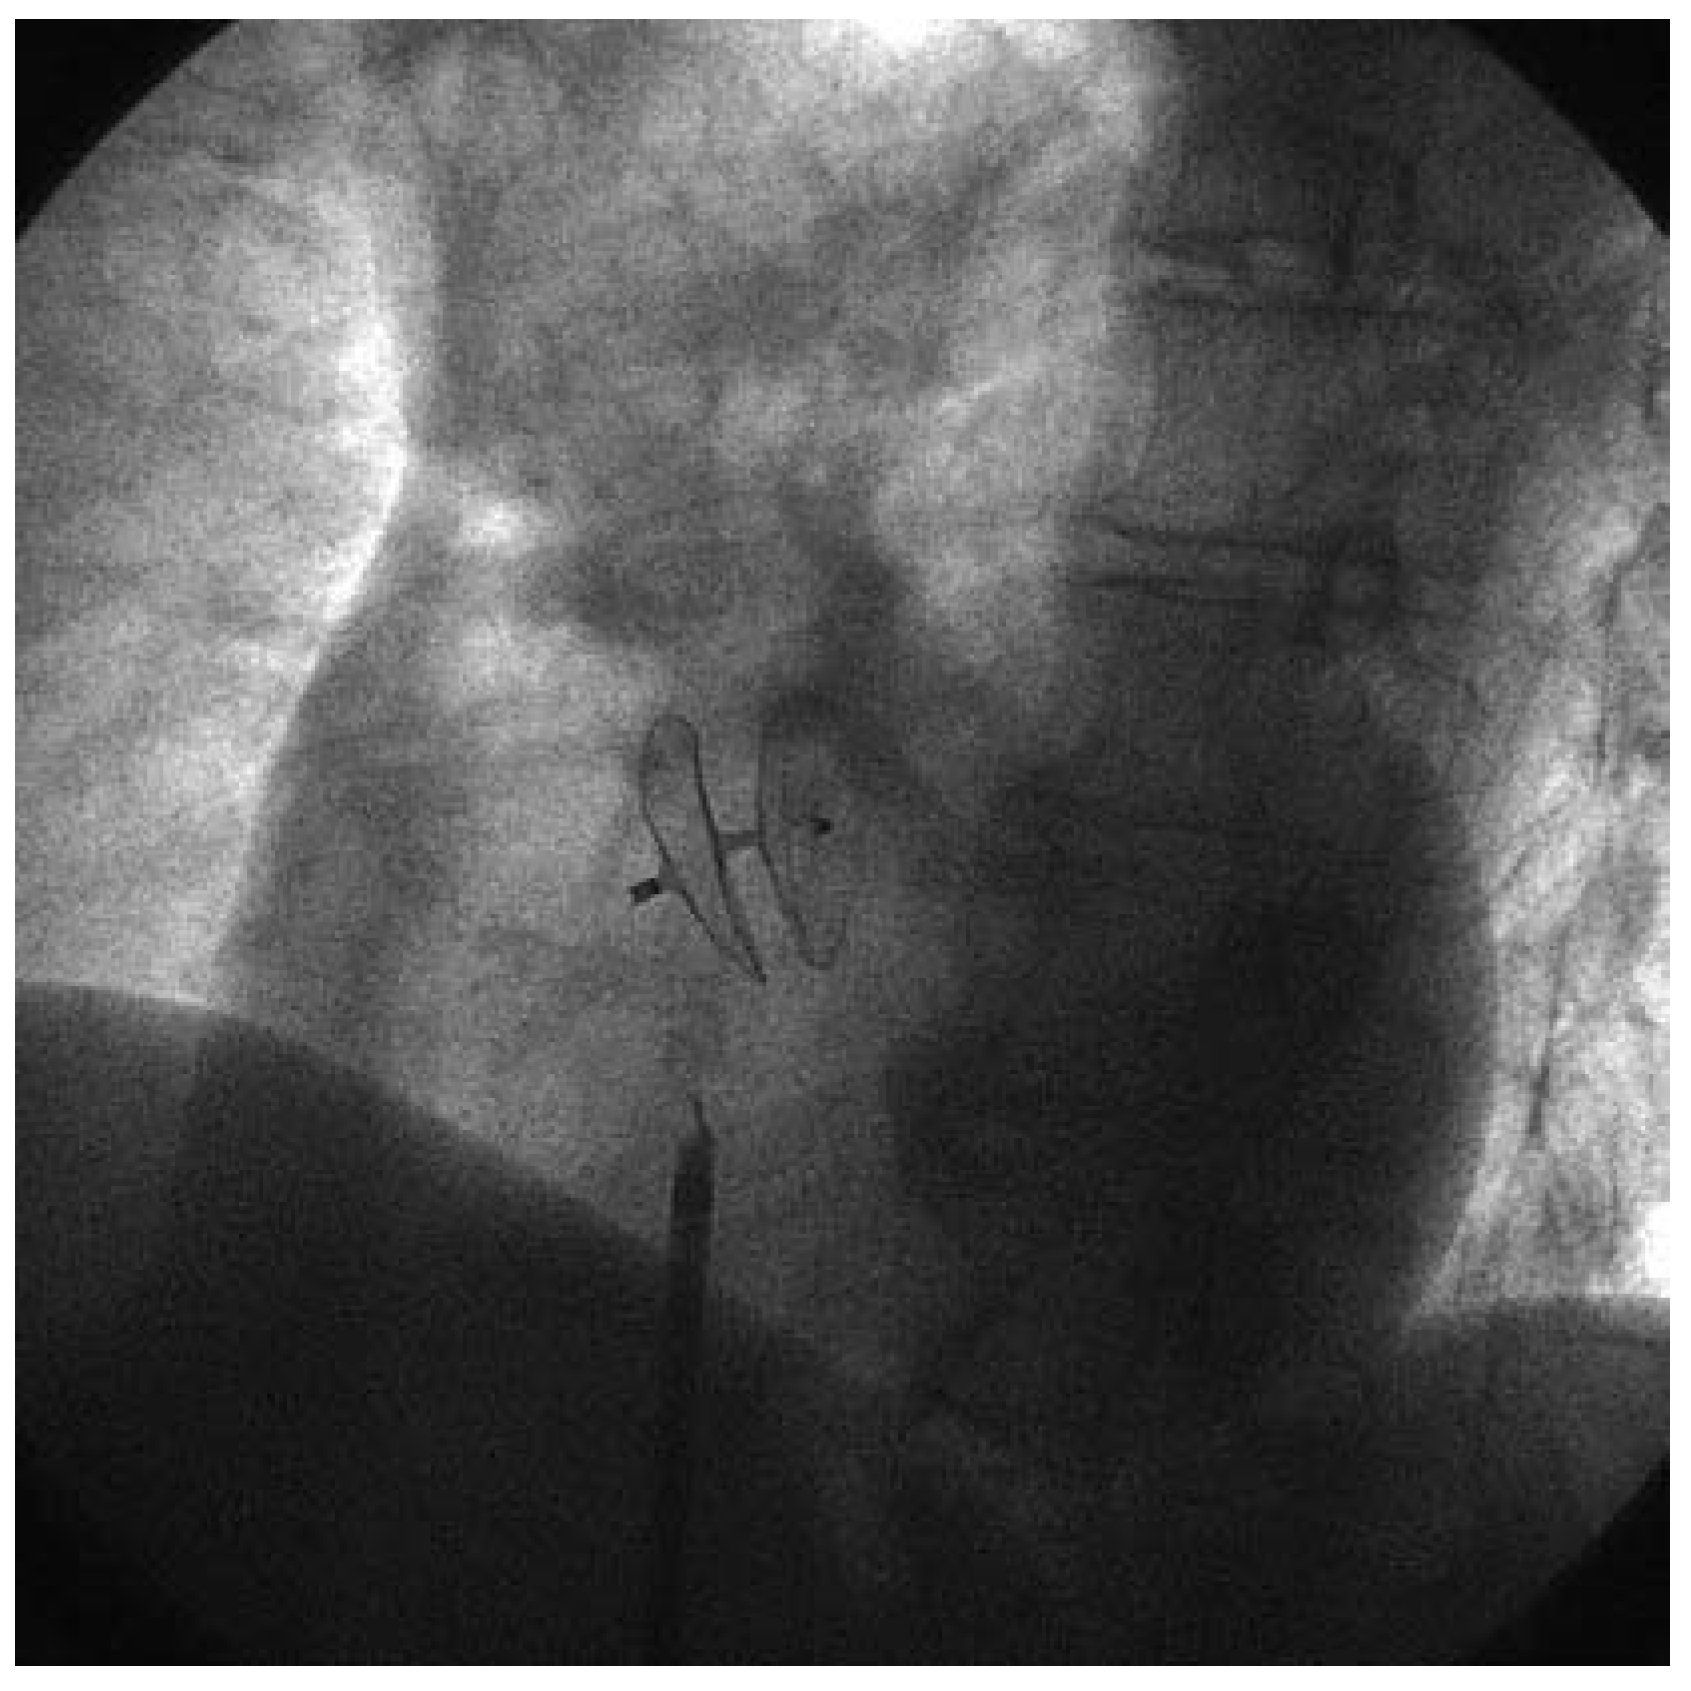

Neben den Klappenleiden sind auch kongenitale Defekte im Herzen, wie beispielsweise ein offenes Foramen ovale, ein Vorhofseptumdefekt, ein persistierend offener Ductus botalli und weitere Leiden von Bedeutung. Das offene Foramen ovale ist besonders häufig und bei den allermeisten Patientinnen und Patienten klinisch stumm. Bereits im letzten Jahrhundert haben die Pathologen auf die Häufigkeit eines persistierend offenen Foramen ovale hingewiesen, jedoch wurde lange Zeit ein solcher Befund als unbedeutend erachtet. In den letzten Jahren allerdings häuften sich Berichte über paradoxe Embolien durch ein offenes Foramen ovale. Die Embolie solcher aus den grossen Venen stammenden Thromben ins Gehirn kann zu klinisch bedeutsamen Komplikationen führen, zum Teil auch bei jüngeren Patientinnen und Patienten. Entsprechend wurden in den letzten Jahren zunehmend echokardiographische Untersuchungen bei diesen Patientinnen und Patienten im Hinblick auf die Entdeckung eines offenen Foramen ovale durchgeführt. Technisch lassen sich heute diese persistierenden Defekte mit verschiedenen Verschluss-Devices verschliessen (

Figure 2). Obschon bei einzelnen Patientinnen und Patienten grosse Thromben auch in situ dokumentiert wurden, ist die Bedeutung der paradoxen Embolien bei unklaren transient-ischämischen Attacken und Hirnschlägen weiterhin umstritten. So wird diskutiert, ob bei Migräne ein offenes Foramen ovale entsprechende Attacken auslösen kann, beispielsweise durch den Durchtritt von Serotonin und anderen bei diesem Leiden implizierten Mediatoren. Obschon zahlreiche Fallberichte und kleinere Serien die Durchführbarkeit und Sicherheit dieses Eingriffes dokumentiert haben, ist der breite Einsatz immer noch in Diskussion, zumal eine randomisierte internationale Studie zwar läuft, aber noch nicht abgeschlossen werden konnte.

In diesem Heft der «Kardiovaskulären Medizin» berichten Gonnella et al. über die günstigen Wirkungen des Verschlusses eines offenen Foramen ovale mit dem Intrasept-Device bei Patientinnen und Patienten mit Migräne [

2].